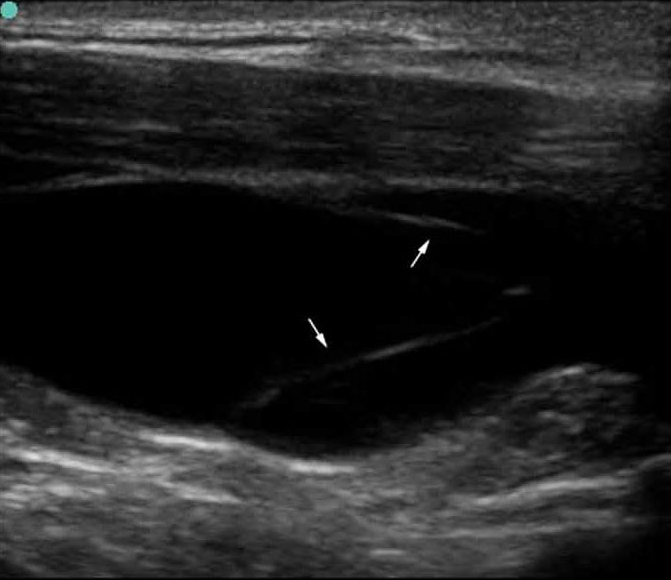

S Series:IJV 长轴(瓣膜打开)。